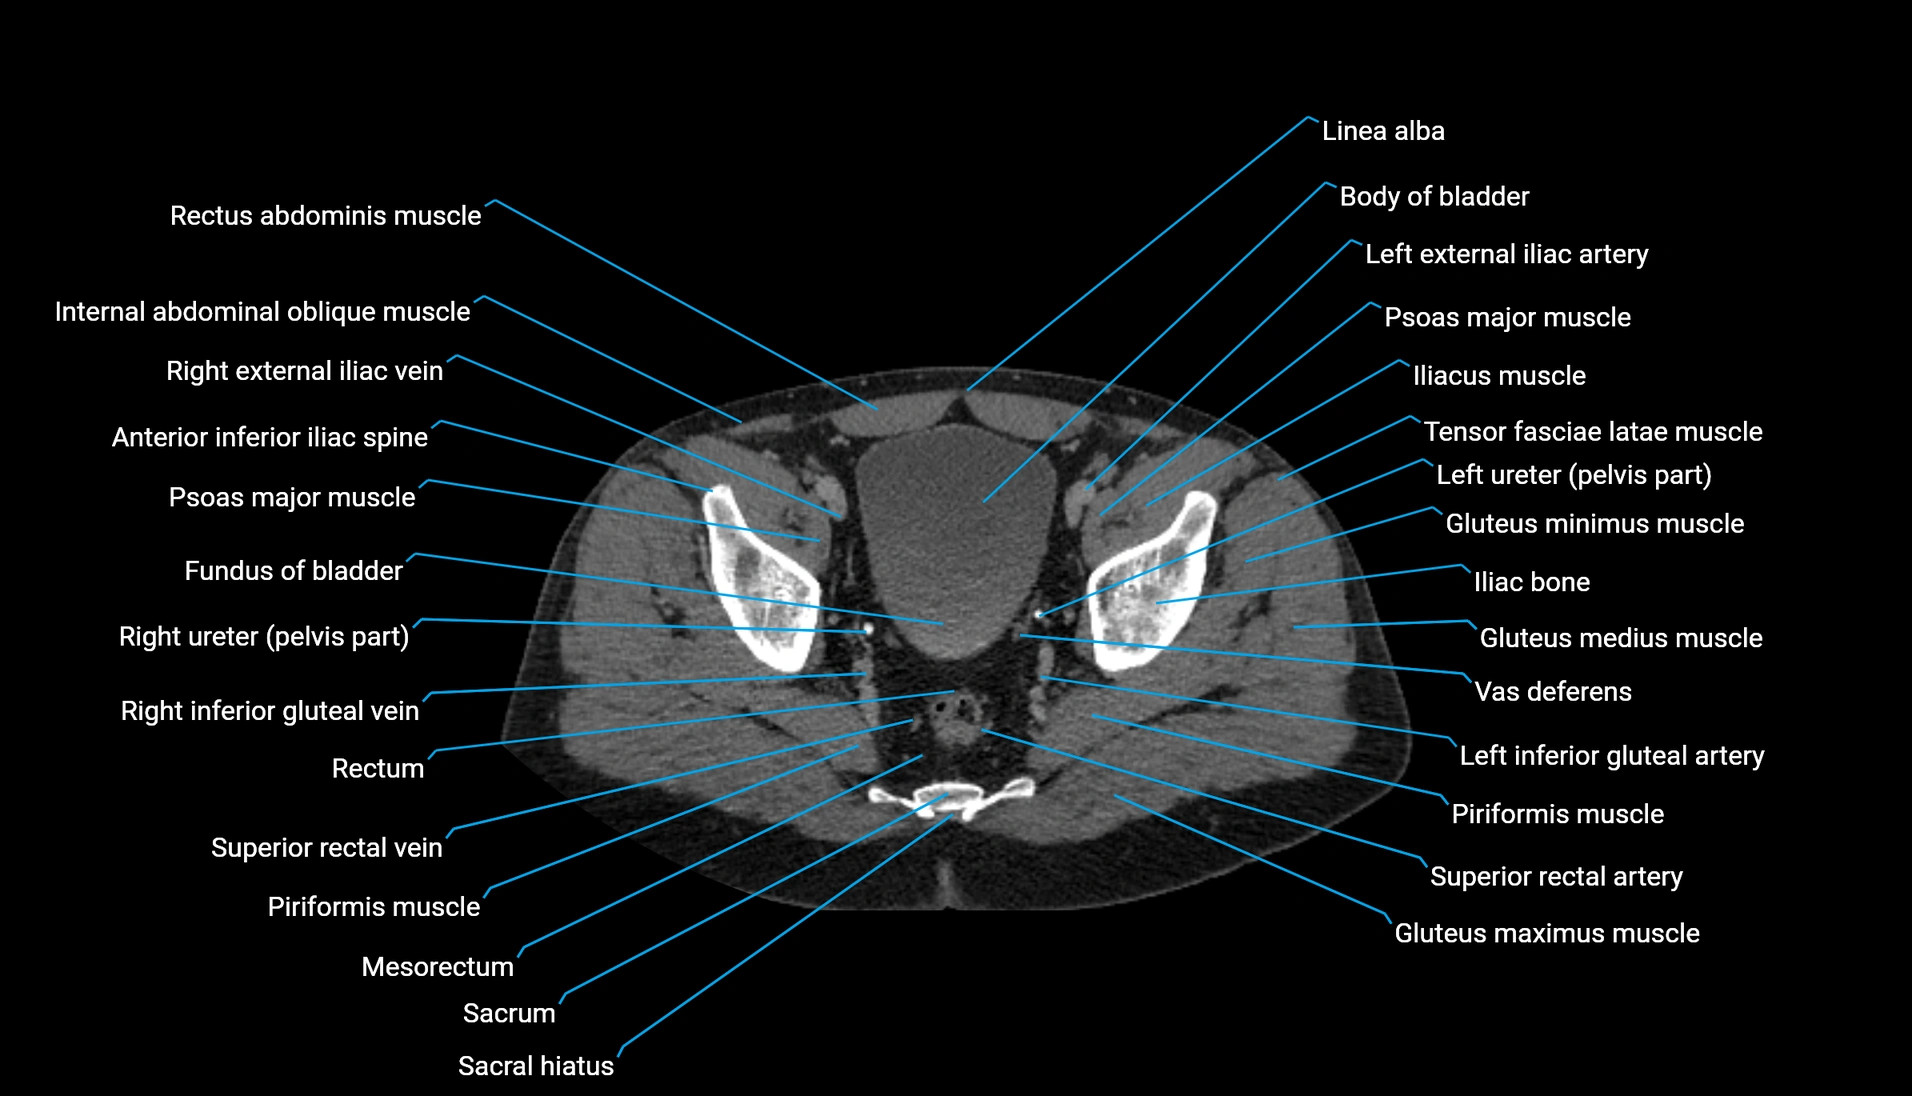

CT Appearance

Non-contrast CT:

-

Demonstrates cortical bone of acetabular rim in excellent detail

Detects fractures, dysplasia, retroversion, or bony overcoverage (pincer impingement)

3D reconstructions used in preoperative hip surgery planning

CT VRT 3D image

CT image